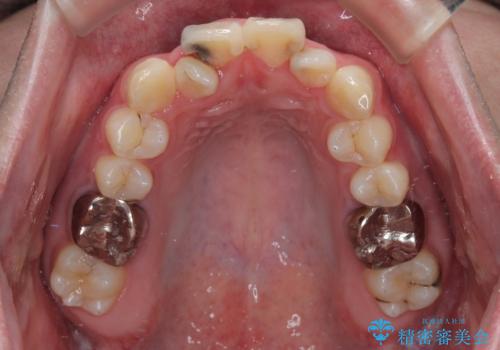

初診時の状態

・上下ともに歯がきれいに並びきらず、がたつきが見られました。

・上下の前歯の中心(正中)がずれています。

・特に上顎の幅が狭いため、下顎の歯列も内側に入り込み、歯が並ぶスペースが不足していました。